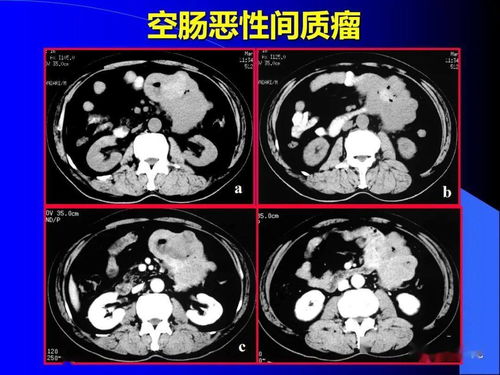

接下来,让我们转向那些较为凶猛的骨肿瘤。骨肉瘤,是青少年最常见的原发性恶性骨肿瘤,它的进展迅速,疼痛剧烈,甚至在静息和夜间也会加重,尤其容易转移到肺部。尤文肉瘤,也是儿童和青少年的常见病症,其症状与骨肉瘤相似,需要通过病理进行鉴别。而软骨肉瘤则可能由良性软骨瘤恶变而来,表现为膨胀性骨质破坏,在四肢更为常见。